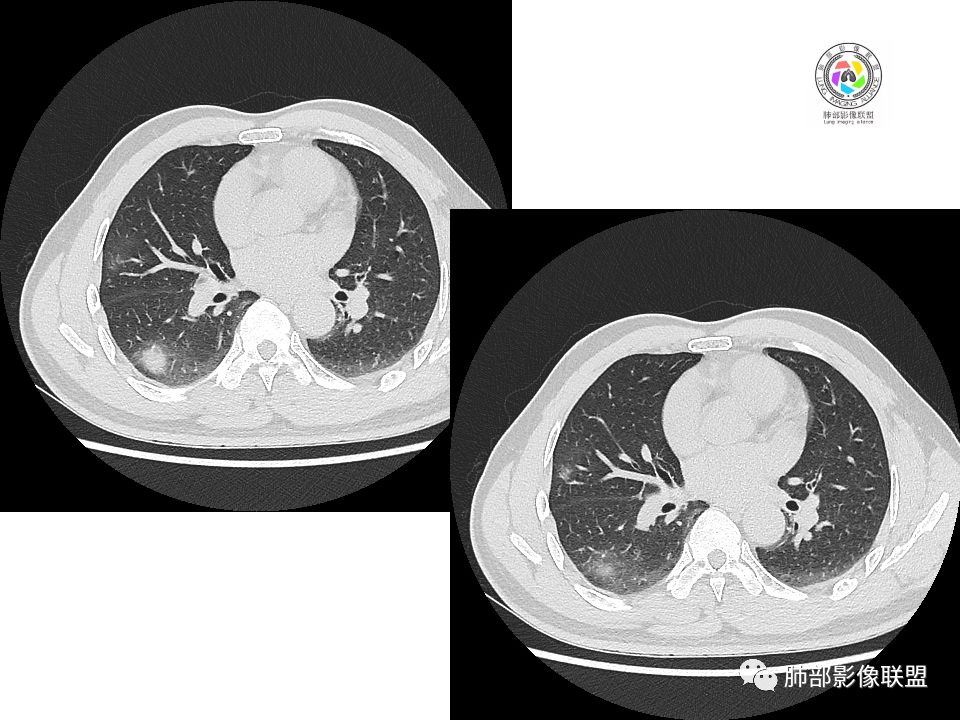

右肺下叶背段胸膜下见团块影,边缘清,其后基底段见一扁平状结节,各见‘’平直及桃尖"征,均轻度强化,右肺上叶背段及中叶外侧段分别少许纤维化灶及部分卫星病灶,一元考虑TB,与隐球菌鉴别!

右肺下叶胸膜下类圆形团块,边缘光滑无毛刺分叶,强化均匀无坏死,另血管旁小结节平直桃尖,上叶小斑片影,考虑结核或者真菌感染。

右肺下叶背段胸膜下见一边缘稍模糊、浅分叶结节灶,密度均匀,似乎轻度均匀强化(具体CT值看不出来),与胸膜锐角相贴,似有平直征和桃尖征。此病灶前内侧还有类似小结节,轻度强化,右肺上叶后段有斑片状稍高密度影:考虑良性病变,炎性结节可能。

晨读,右肺下叶背段胸膜下见肿块影,边缘清晰,未见与气管相连通,右下叶见结节影边缘清晰,两处病变密度均匀,同步不明显强化,中叶外侧段斑点状影,树芽征,考虑1良性病变,结核?隐球菌?2淋巴瘤待除外。

右肺下叶背段胸膜下宽基底团块状占位,浅分叶,边界清晰,胸膜下脂肪间隙清晰,背段支气管管壁似乎增厚,未见明显强化。外侧基底段血管束间结节,边界清晰,亦未见明显强化。中叶外侧段见少许树芽征象。纵隔未见明显肿大淋巴结。我先猜个结核。

男性,49岁,体检发现,右肺下叶背段胸膜下见肿块,边界清楚,边缘光滑,胸膜下脂肪间隙存在,有分叶,无毛刺,均匀强化,内无坏死,右肺下叶血管束间不规则实性结节,边界清楚,无明显强化,中叶少许斑片状高密度影,纵隔未见明显增大淋巴结,考虑良性病变。